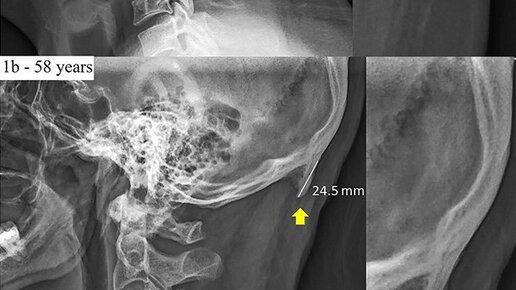

Первый вариант. Если потрогать рукой область головы сзади, где кончается шея и начинается голова, то некоторые люди могут нащупать некую шишку, маленькую выпуклость. Эта штука известна в узких кругах еще как и «математическая шишка». Она, якобы, даёт математические способности. Но это скорее всего нечто иное просто такое строение черепа заложенное генами от потомков. Второй вариант. В середине 19 века австро-венгерские антропологи обнаружили, так называемую косточку тюрка. Её научное название Tuberculum Turcum, также ее называют Central Asian Crainial Ridge...